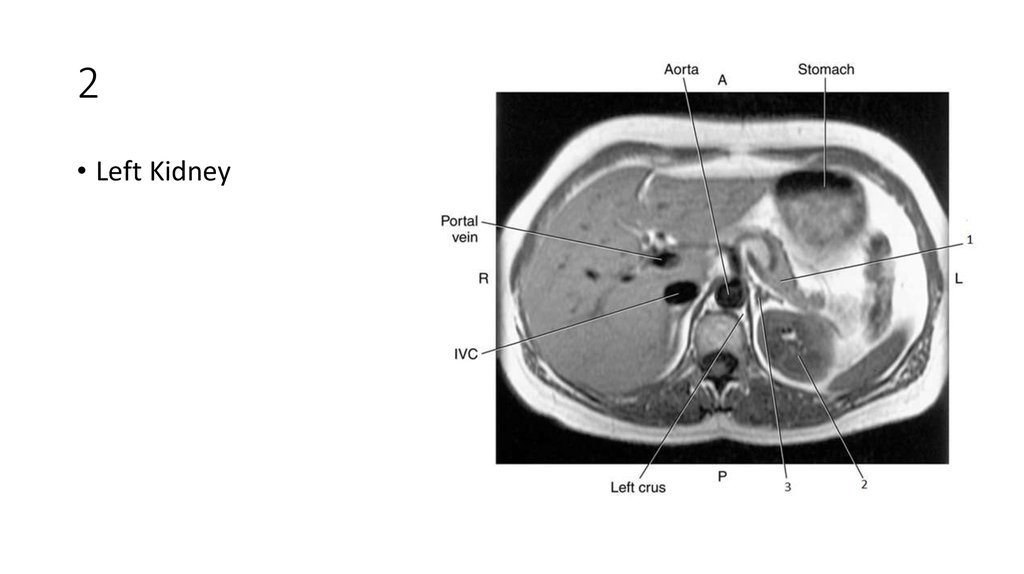

46. 2

47. 2

• Left Kidney